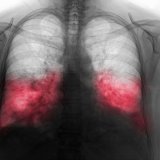

„Kokičasta pluća“ je uobičajeni naziv za retko, ali ozbiljno stanje pluća poznato kao bronhiolitis obliterans. Oštećuje male disajne puteve u plućima, otežavajući disanje. Ovaj nadimak je nastao početkom 2000-ih, kada su radnici u fabrici kokica za mikrotalasnu rernu razvili ovo stanje nakon dugotrajne izloženosti hemikaliji dijacetilu, koja se koristila za davanje puterastog ukusa kokicama.

Dijacetil je najpoznatiji uzročnik, ali nije jedini. „Kokičasta pluća“ mogu da se razviju i nakon izlaganja drugim toksičnim isparenjima, hemikalijama ili kao komplikacija respiratornih infekcija.

Poslednjih godina, vejpovanje je povezano sa ovim stanjem, jer je u nekim tečnostima za vejp i aromatizovanim proizvodima pronađen dijacetil ili slične štetne supstance. Udisanje ovih materija može vremenom nadražiti i oštetiti disajne puteve u plućima.

Ovo stanje se ne razvija preko noći. Rani simptomi uključuju uporan suv kašalj, kratak dah, šištanje pri disanju i umor — što se često pogrešno tumači kao astma ili bronhitis. Međutim, oštećenje je progresivno i nepovratno ako se ne dijagnostikuje na vreme.